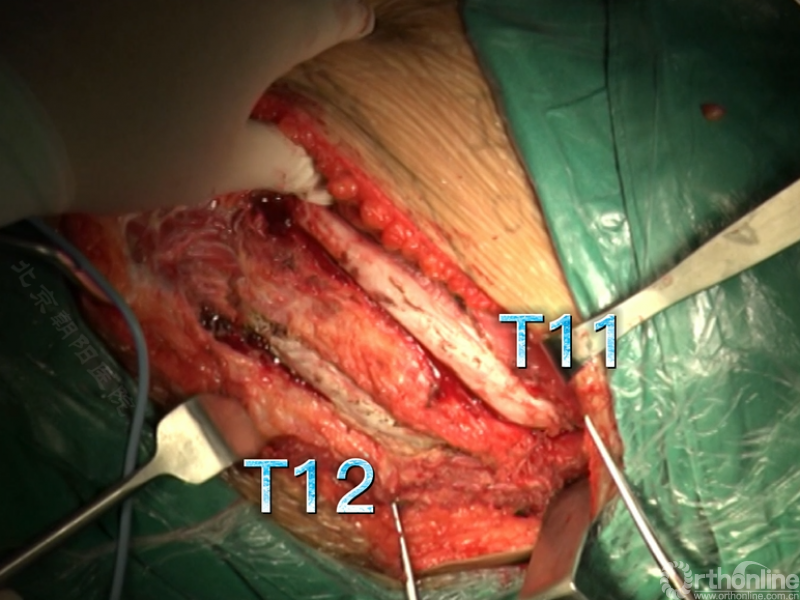

经近端需内固定的椎体(T11)相对应的肋骨表面做一弧形切口,分离浅层软组织直至肋骨表面的多层肌肉组织,切口止于脐的远端偏外侧。

骨膜下环形剥离完整显露肋骨。

切开第11肋骨肋软骨的连接部,并将肋骨靠近脊柱的部位切断。

同理将第12肋骨摘除。